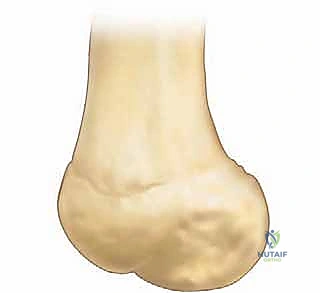

The macroscopic dimensions of the native MPFL are highly consistent across the adult population. It measures approximately 58 mm in length, with an average width of 12 mm and a remarkably thin cross-sectional thickness of roughly 0.44 mm at its midpoint. From its femoral origin, the ligament fans out anteriorly, broadening as it approaches the patella. Its insertion footprint covers the proximal two-thirds of the patella's medial margin, transitioning from a distinct ligamentous band into a broader retinacular expansion. Recognizing this broad patellar footprint is critical; a point-to-point repair using a single anchor often fails to recreate the native biomechanics, necessitating a dual-anchor technique to restore the broad insertion.

Preparation of the patellar bed is a critical step for biologic healing. The native insertion site on the proximal two-thirds of the medial patellar facet is exposed. Using a curette, rongeur, or a high-speed burr, the medial cortical margin is lightly decorticated down to bleeding cancellous bone.

This bleeding bed provides the necessary marrow-derived mesenchymal stem cells and growth factors to facilitate robust ligament-to-bone healing. Two suture anchors (typically 4.75 mm or smaller, biocomposite or PEEK) double-loaded with ultra-high-molecular-weight polyethylene (UHMWPE) sutures are then placed into the decorticated patellar margin. The anchors are spaced appropriately (one proximal, one distal) to recreate the broad native footprint.